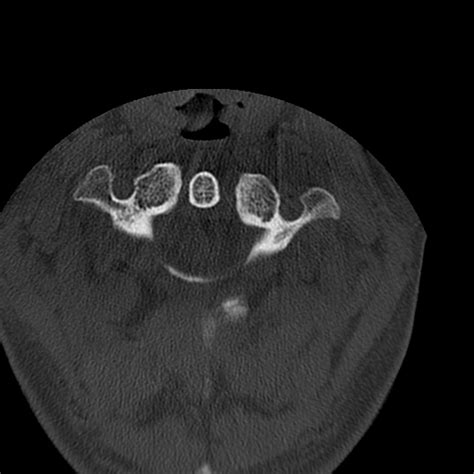

• Computed Tomography (CT) Scan: This is the gold standard for diagnosing occipital condyle fractures. CT scans provide detailed images of the bony structures and can help identify the location and extent of the fracture.

Occipital condyle fractures are classified based on their pattern and mechanism of injury. The most commonly used classification system is the Anderson and Montesano classification, which categorizes these fractures into three types:

Type III Avulsion fracture of the occipital condyle Altered rotational forces